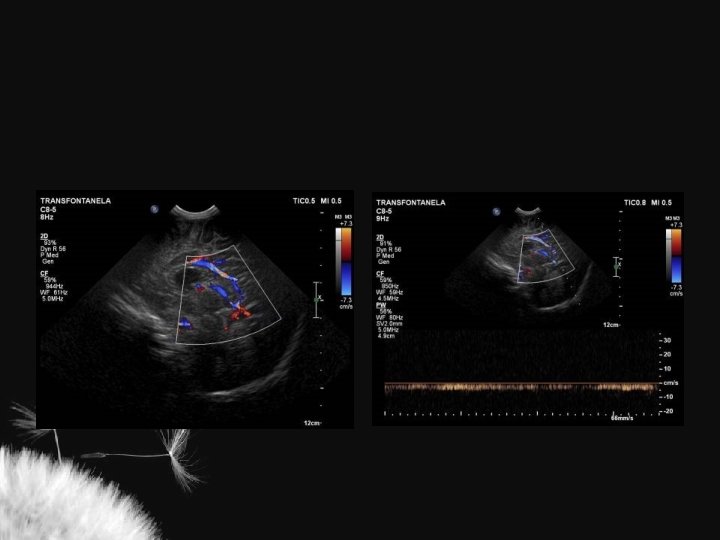

Hidrocefalia benigna da infância – sinal da veia cortical positivo

Coleção subdural – sinal da veia cortical negativo